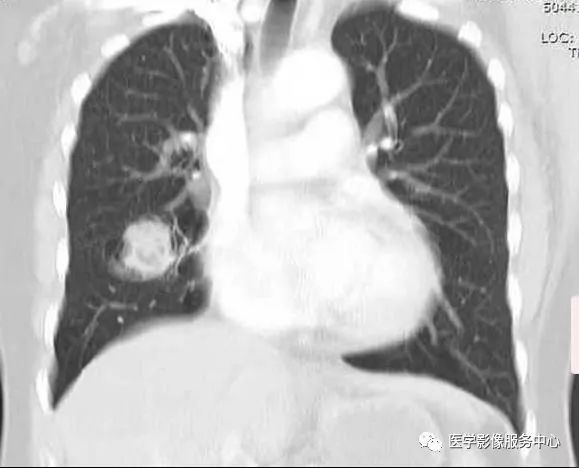

CT:右肺中叶见一个球形软组织密度影,周围见空气新月征

(1)致密阴影在空洞内随体位的改变而移动。在直立的胸部x线片,空气新月征位于致密阴影上;然而,在患者仰卧的CT图像上,空气新月征位于致密阴影前。

该患者右肺中叶切除术后,病理:肺曲菌球

CT:初为肺部局限性炎症,表现为斑片状模糊阴影,继发周围炎症吸收,表现为团块状或结节状阴影,周围环以浅淡的磨玻璃样的晕,当肺组织液化,坏死物咳出后,则表现为:新月状的空气所包绕的一致密阴影,该致密阴影边缘光整,密度较均匀,增强无强化,且致密阴影在空洞内随体位的改变而移动。